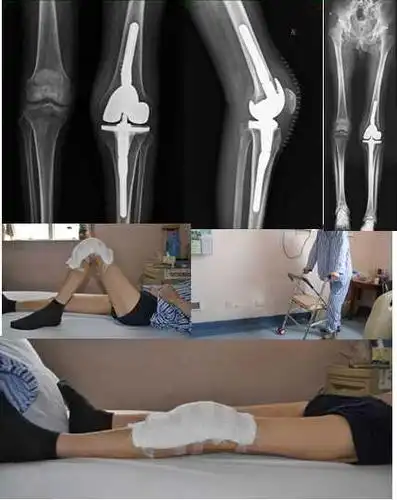

术前右膝被动屈伸活动角度:10-60度;主动:15-30度

术后膝关节可伸直,外观及活动度满意,已经下床功能锻炼.